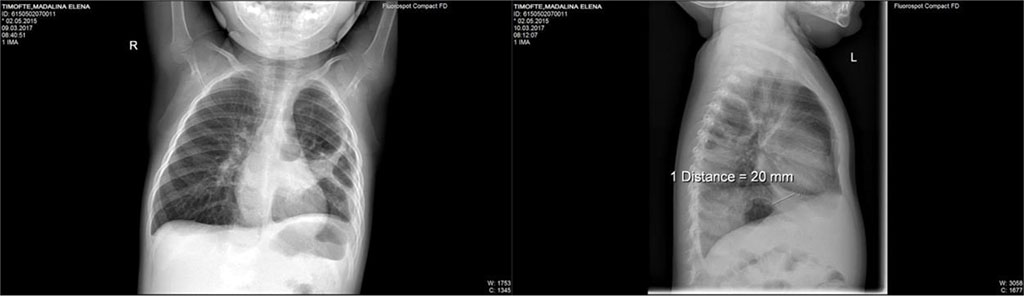

Thus, we’ve decided to change from Ceftriaxone to Piperacillin/ Tazobactam. With this new treatment the child had a good evolution both clinical and biological (inflammatory markers decreased significantly). After 8 days with this new antibiotic treatment, the patient resumes symptoms of productive cough, dyspnea, wheeze and rhonchi across the left lung area. Repeated blood tests showed an important increase of CRP. Repeating the X-ray, we saw a transparent lesion of 35/24mm, circled by a 3mm peripheric opaque ring located in the posterior side of left-superior lobe. (Fig.2)

Fig. 2. Transparent lesion of 35/24mm, circled by a 3mm peripheric opaque ring located in the posterior side of left-superior lobe; two air-fluid levels of 8mm and respectively, 40mm located at the posterior basis of left lung

Control chest X-ray described mild interstital infiltrate of both lungs; two radiotransparent lesions that appear to communicate onthe superior located near heart.